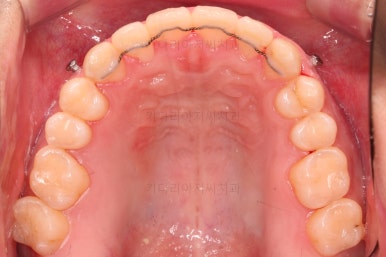

초진 시 입안의 모습입니다.

교합이 많이 안좋습니다.

위아랫니가 서로 엇갈려 가며 지그재그로 껴 들어가야 어금니 맞물림이 생기는데요.

이번 환자분은 아랫니, 아래턱이 전반적으로 앞으로 나와 있어서 교합이 전혀 안되고 있는 상태였습니다.